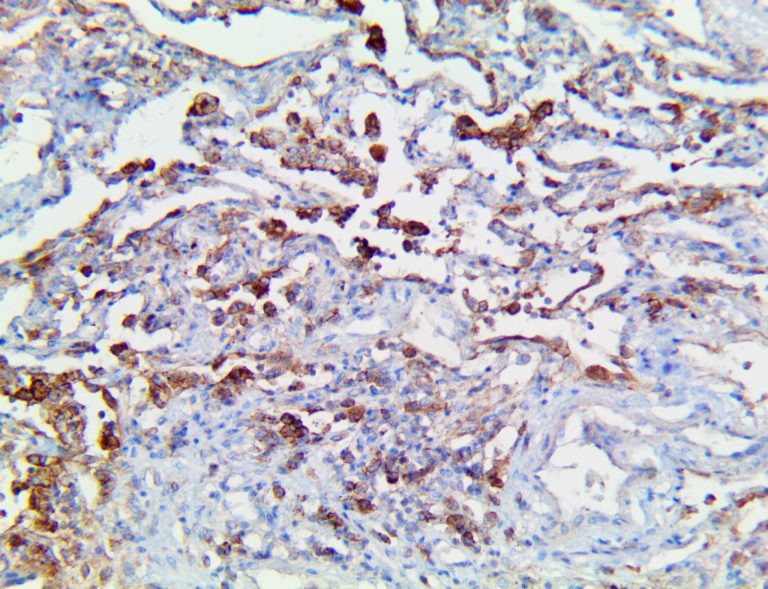

The first cytokines released are interleukin 1β (IL-1β) and tumor necrosis factor-α (TNF-α), which attract a variety of circulating white blood cells (WBCs) to the infection site, including neutrophils, monocytes, macrophages, and natural killer (NK) cells. This response, along with the antipathogenic chemicals released by these cells (i.e., complement), comprise the innate immune response. These cells directly attack the invading pathogen and also release additional cytokines, chief among them interleukin-1 and 6 (IL-6). IL-6 is essential for invoking the adaptive immune response, which calls T-cells, B-cells, and T helper (Th) cells to the infection site. IL-6 also stimulates further recruitment, proliferation and activation of macrophages.

This activation induces inflammatory monocytes to highly express IL-6, starting a localized and then systemic cascade effect that results in hyperproduction of IL-6, which accelerates the inflammatory process. Because IL-6 also increases vascular permeability, excessive levels cause blood vessels to become very leaky. This, along with clotting factors released from vascular endothelial cells, stimulates the coagulation cascade, resulting in microthrombosis (tiny clots), which leads to ischemia and tissue death of the kidney, intestines, heart, liver, brain and extremities.